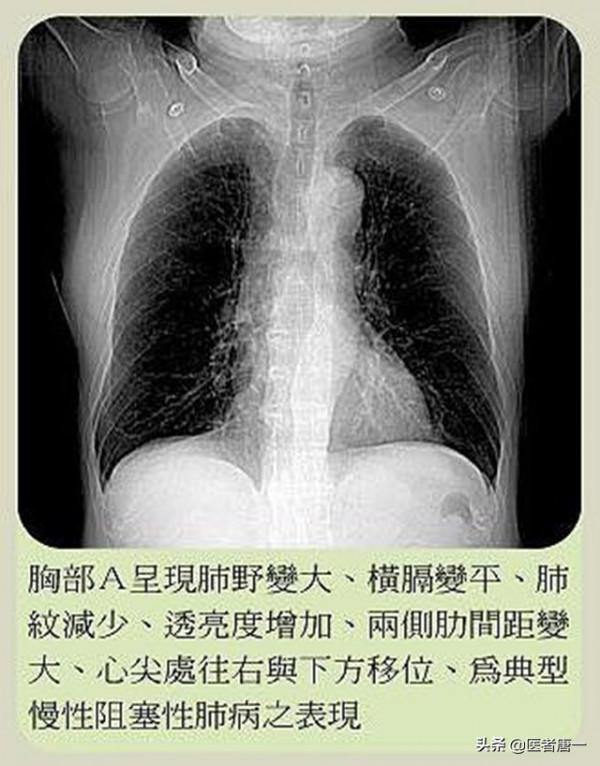

透過李叔叔的描述以及CT和肺功能的結果,醫生最終給李叔叔診斷為“慢性阻塞性肺疾病”,也就是平時老百姓常說的“老慢支”。由於李叔叔正處於急性炎症期,醫生便建議李叔叔住院治療幾天。在住院的這幾天,李叔叔除了接收消炎治療外,每天都會有護士長親自帶著他們慢阻肺的病人們一起做呼吸鍛鍊,從吹氣球,到呼吸操,再到唱歌。